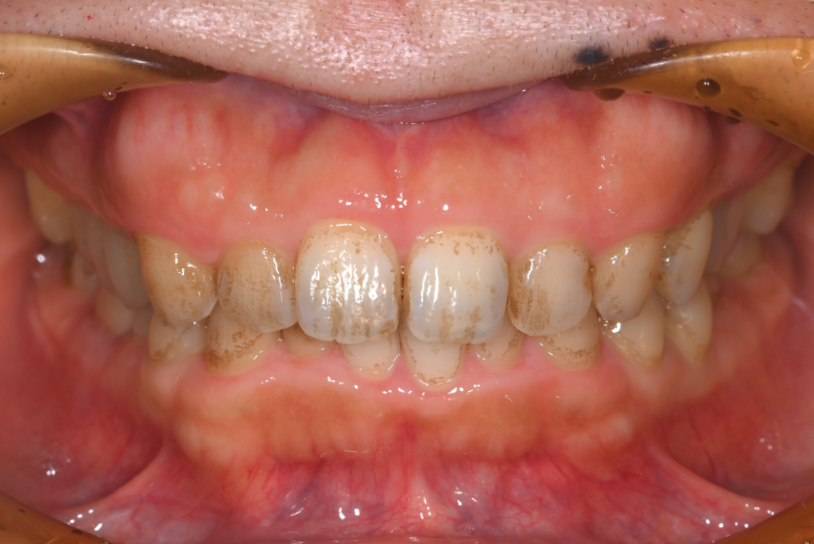

上下顎臼歯部にう蝕と全顎的な着色を認めたので、う蝕部位をE-maxで治療した後、PMTCによる着色除去を計画しました。

う蝕により黒くなっていた臼歯部はE-maxインレー(セラミックインレー)にて修復し、歯科衛生士によるPMTCで歯面に付着した着色を除去しました。

治療終了時、患者様には着色の無いきれいなご自身の歯に大変満足して頂きました。